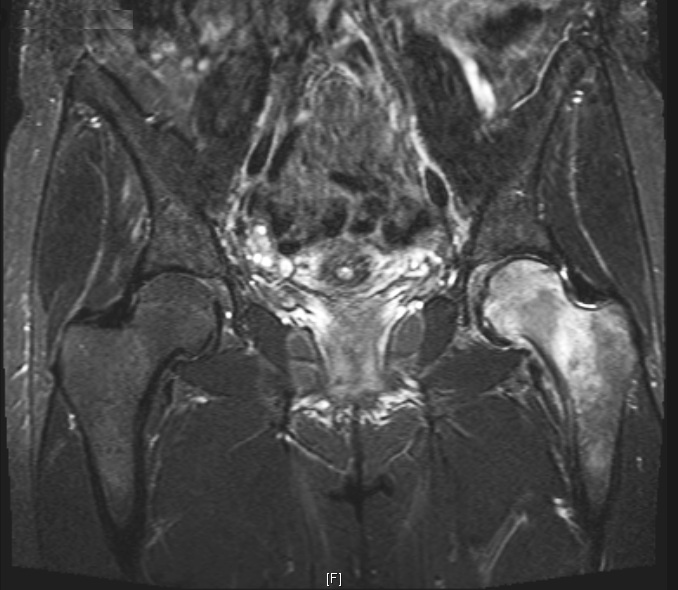

MRI scans show characteristic changes with decreased signal intensity of bone marrow on T1-images, increased signal intensity relative to the intensity of normal marrow on T2-images and joint effusions are characteristically seen on T2-images. There may be crescent lines but when studied these all resolve without progressing to AVN.